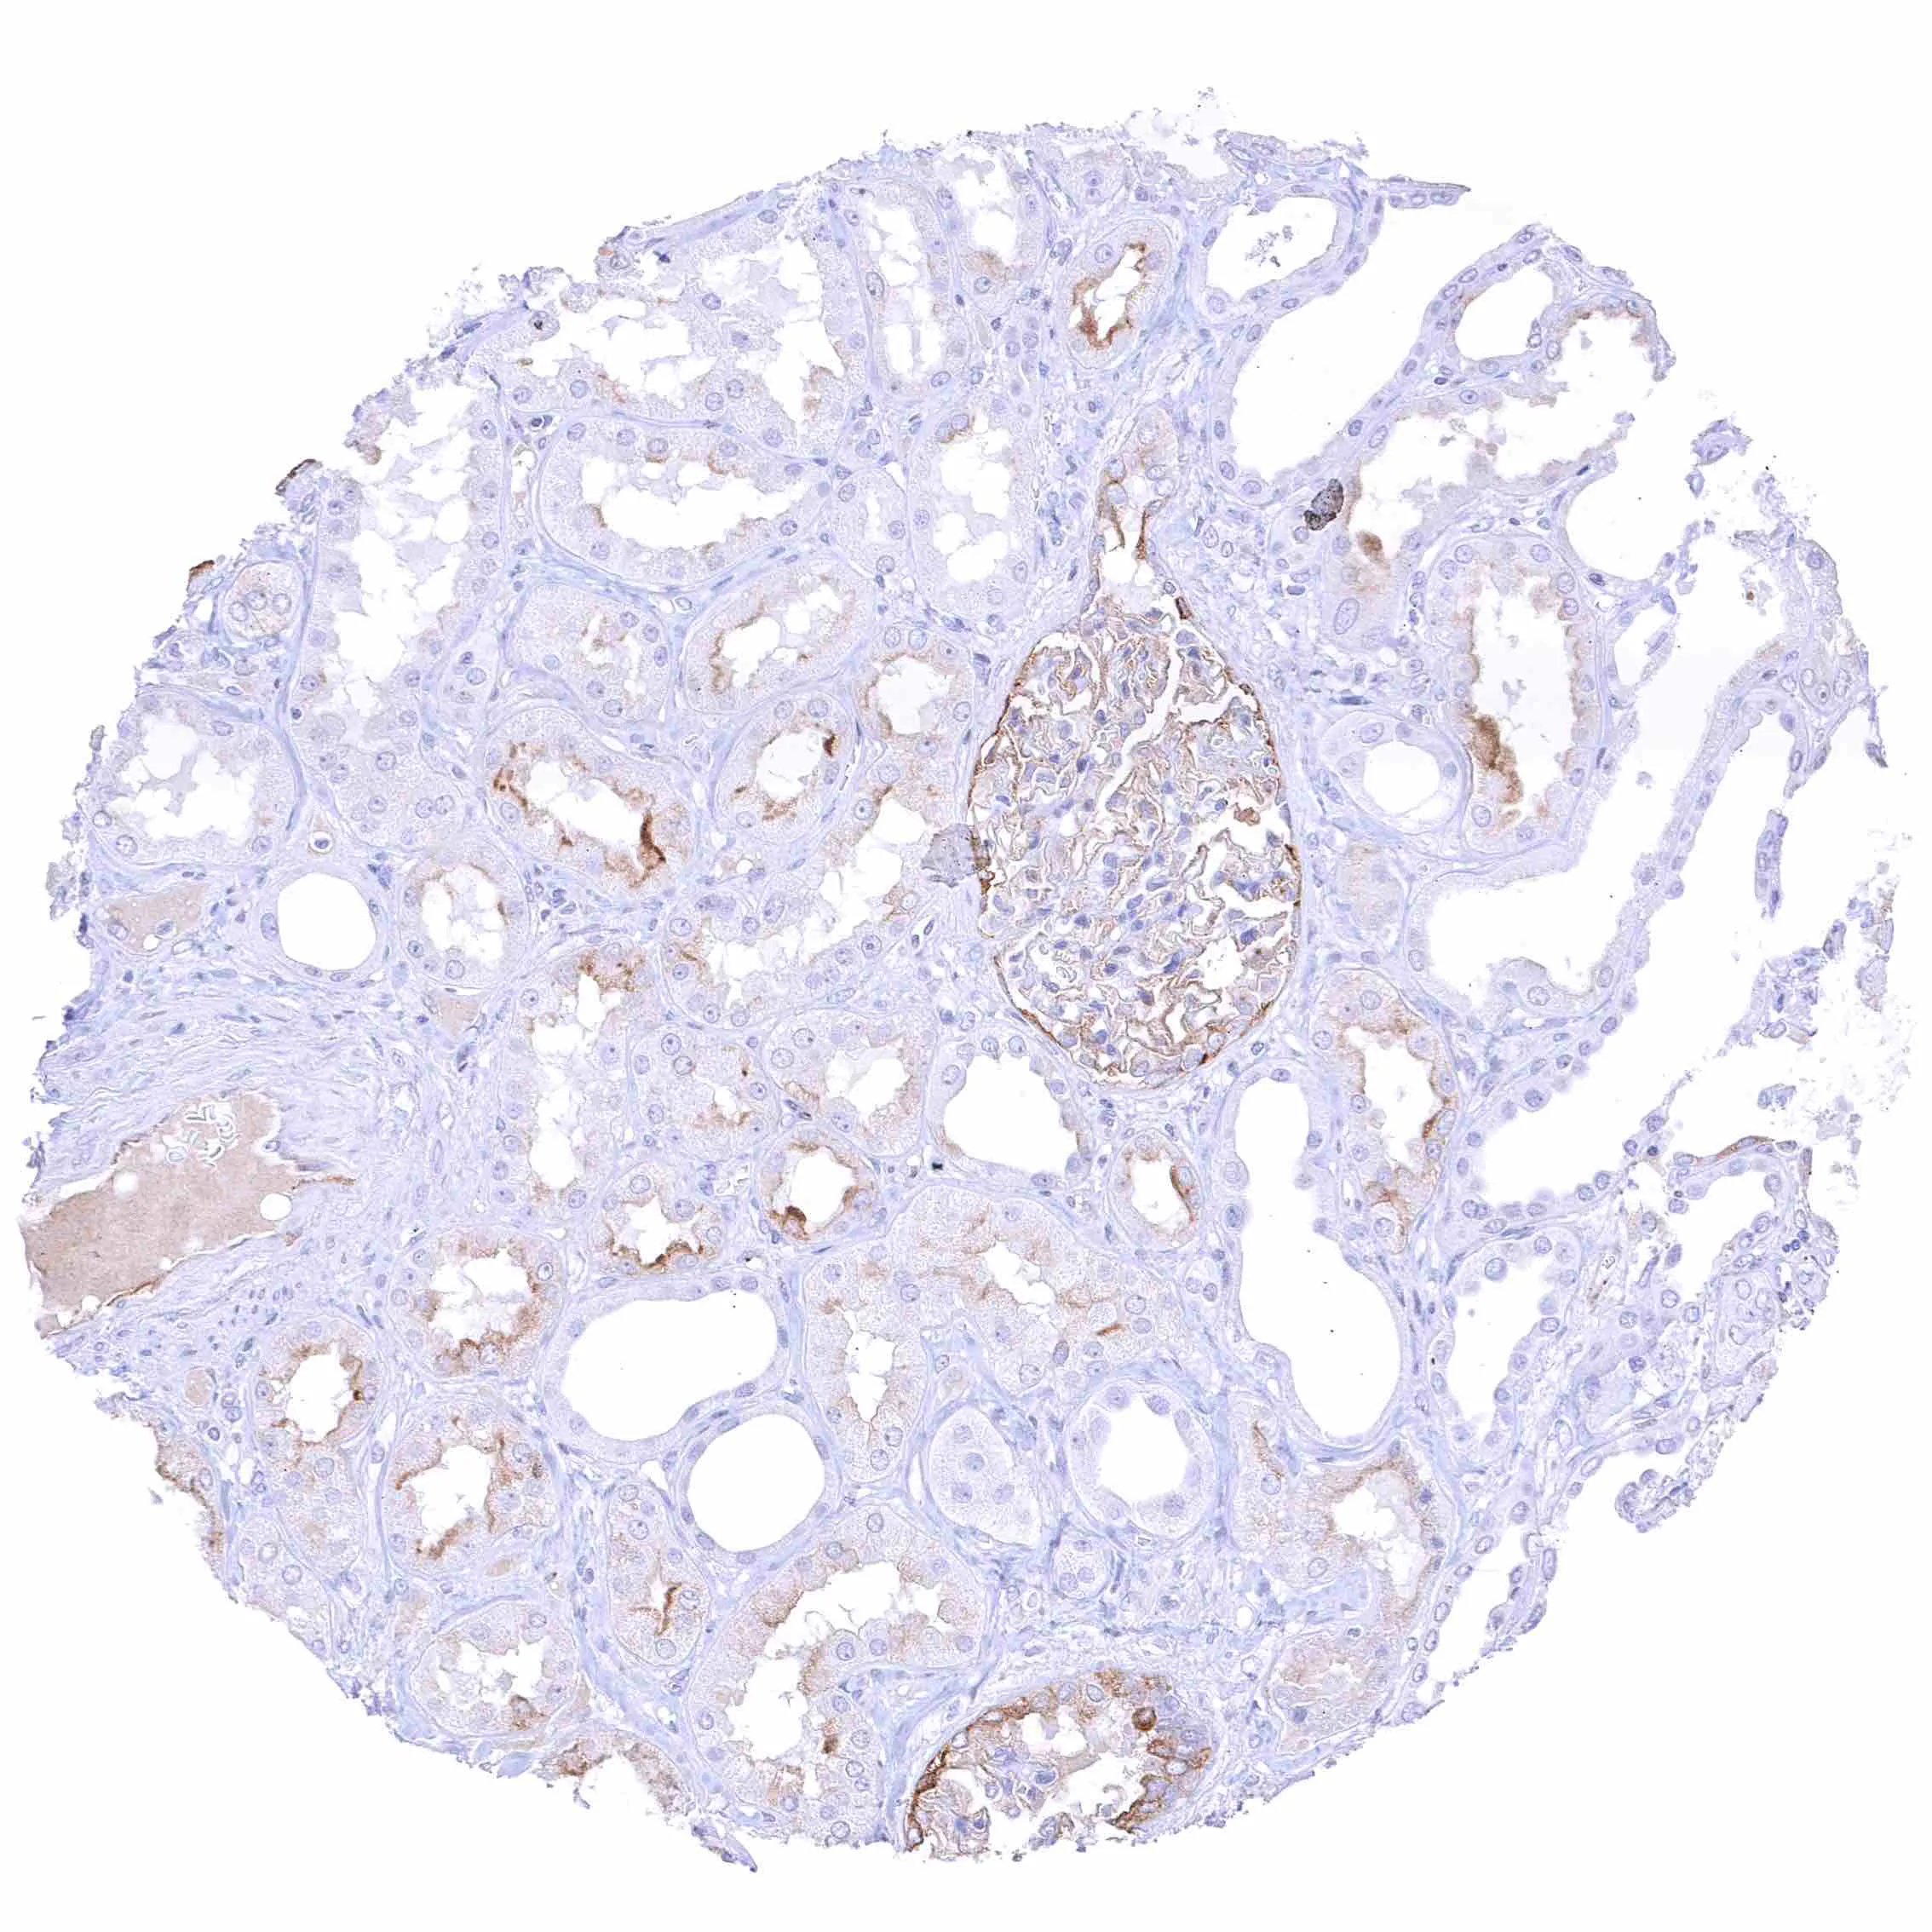

Lung – Faint membranous NPR-C staining at the luminal cell border of some endothelial cells.